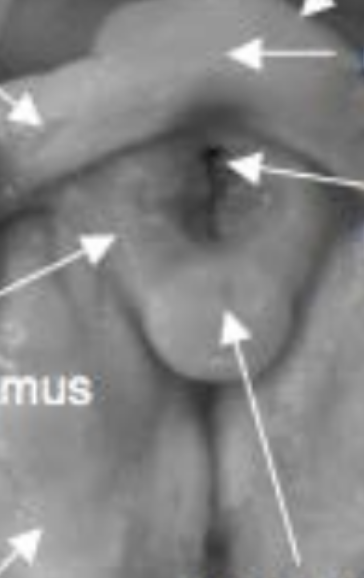

Hypothalamus

A

Motivation + the 4 Fs (feeding, fleeing, fighting, fornicating)

Mammillary bodies

Memories